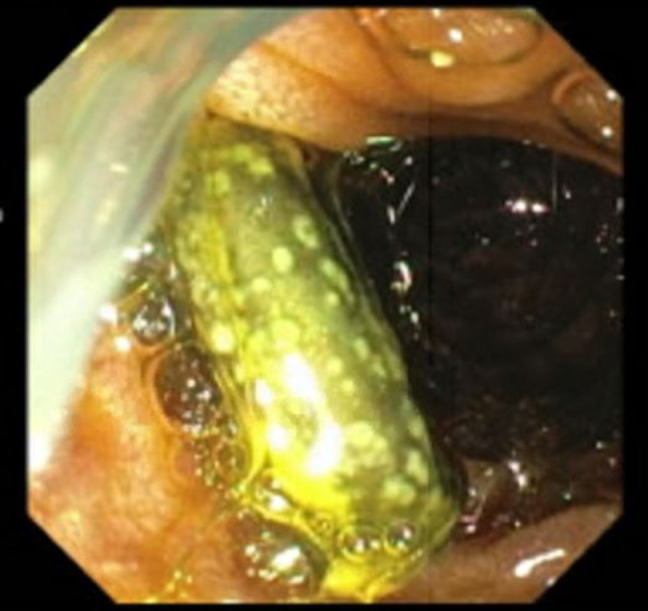

The patient was a 29-year-old man who initially presented to our center with concerns of generalized body aches and was found to have a column of air within his transjugular intrahepatic portosystemic shunt (TIPS) stent and a fistulous connection between his common bile duct (CBD) plastic stent and uncovered metal TIPS stent (Figure 1). He had a history of chronic portal venous thrombosis in the setting of a hypercoagulable state from systemic lupus erythematous with a positive lupus anticoagulant. This led to cavernous transformation resulting in portal biliopathy with complications of recurrent ascending cholangitis, bacteremia, and abscess formation. This was managed with multiple CBD stents and eventually a TIPS procedure with an uncovered stent at an outside center.

For unclear reasons, the plastic CBD stent was not replaced for over a year and the patient had declined prior surgical interventions such as a mesocaval shunt. When he presented to our center, the patient had abdominal pain that was worked up by CT, which showed a column of air within a TIPS stent that was occluded at both the proximal and distal ends with concern for a fistula between the CBD stent and the TIPS stent. The gastroenterology team further evaluated this by endoscopic retrograde cholangiopancreatography (Figure 2), during which time, the CBD stent was removed; a fistulous connection between the prior CBD stent and the uncovered TIPS stent was confirmed; and a covered metal stent was placed in the CBD. The patient also had a new Citrobacter braakii bacteremia during this hospitalization, which further confirmed that the GI enteric flora was able to enter the systemic circulation through the fistulous connection. Further intervention by interventional radiology was impeded by concern that the column of air within the TIPS stent would lead to an air embolus during any procedure. The patient was further evaluated by general surgery and vascular surgery; however, further definitive treatment was deferred in the setting of severe thrombocytopenia secondary to immune-mediated thrombocytopenia. His immune-mediated thrombocytopenia was managed with medical therapy initially but was refractory requiring splenectomy with initial improvement, although later it relapsed. He was discharged with close follow-up with planned outpatient CBD stent exchange.